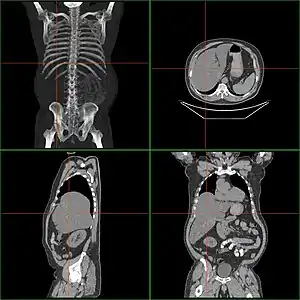

| Computerized tomography of affected person with hepatomegaly | |

Computerized tomography (CT) can give accurate anatomical information for a complete diagnosis.[21]